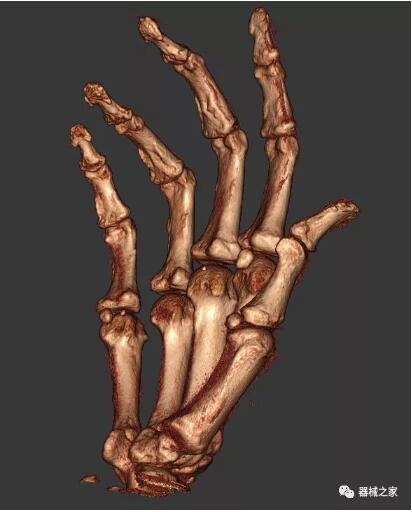

另外一款被稱為世界上最小的CT,它的重量僅300磅,不僅能夠掃查足部,還可以檢查膝蓋和上肢等。

與上面介紹的CT一樣,它同樣具有輻射低、占地空間小(23*36)的特點(diǎn),隨開隨用(支持直接接入墻上的插座)。

這款CT使用非常方便,通過上下移動保持與患者的手臂或者雙腿齊平,掃描快速,僅需要30秒左右就可以完成掃查。

以下是這些“特立獨(dú)行”的CT所拍出來的圖像: